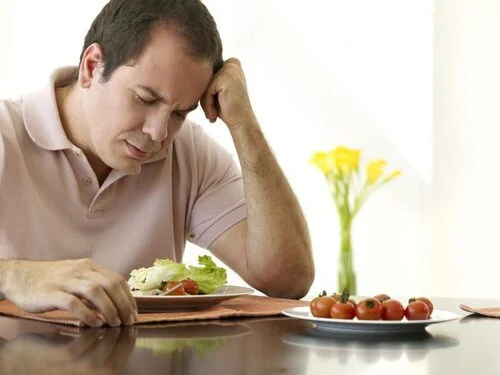

Bệnh nhân bị suy nhược, thiếu hụt chất dinh dưỡng do hoạt động ăn nhai phải chịu nhiều áp lực như đau nhức hay mỏi cơ hàm. Dần dần hình thành cảm giác biếng ăn.

Rối loạn chức năng khớp thái dương hàm (TMD) không chỉ gây đau nhức mà còn ảnh hưởng đến việc ăn uống, nói chuyện và sinh hoạt hằng ngày. Ngoài các phương pháp điều trị chuyên sâu, bạn hoàn toàn có thể cải thiện tình trạng này thông qua chế độ ăn uống hợp lý, các bài tập hỗ trợ và điều chỉnh thói quen sinh hoạt. - CHẾ ĐỘ ĂN UỐNG GIÚP GIẢM ÁP LỰC CHO KHỚP HÀM Việc lựa chọn thực phẩm phù hợp có thể giúp giảm tải áp lực lên khớp hàm và hạn chế các cơn đau do TMD gây ra. - Ưu tiên thực phẩm mềm, dễ nhai: Cháo, súp, sữa chua, trứng, cá mềm, rau củ nấu nhừ. Các loại trái cây mềm như chuối, bơ, dưa hấu. Đậu phụ, thịt xé nhỏ hoặc hầm nhừ. - Tránh các thực phẩm gây căng cơ hàm: Thịt dai, các loại hạt cứng, bánh mì giòn, kẹo cứng. Đồ ăn cần mở miệng rộng như bánh mì kẹp, burger. Nhai kẹo cao su, nhai đá – có thể làm trầm trọng hơn tình trạng đau hàm. - Mẹo nhỏ: Cắt nhỏ thức ăn trước khi ăn để giảm áp lực nhai. Khi ăn, nhai đều hai bên hàm cùng một thời điểm để tránh tạo áp lực không cân bằng lên khớp.